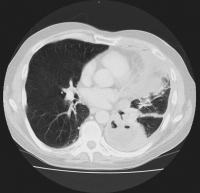

Thorax-CT

Abbildung 1: Präoperatives Thorax-CT bei therapierefraktärer Stenoseproblematik cT2-3cN2cM1 (cereb.)